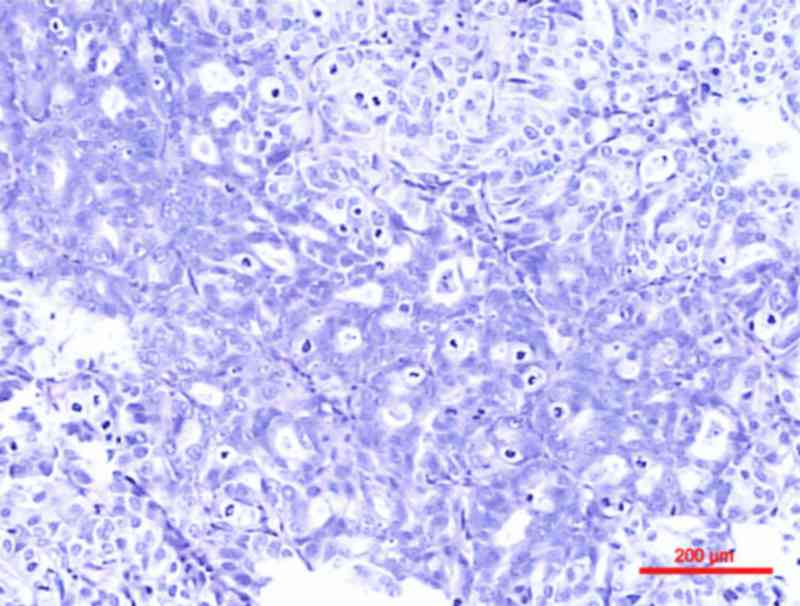

Webpathology.com: A Collection of Surgical Pathology Images. However, the association with urothelial carcinoma remains controversial. Invasive urothelial carcinoma with comedo necrosis. Urothelial carcinoma of the prostate. Abstract upper urothelial carcinoma (uuc) has a plasticity to demonstrate divergent differentiation with squamous metaplastic elements. Urothelial carcinoma with squamous differentiation tends to show more aggressive behavior, a higher risk of recurrence and worse survival outcomes when compared to pure urothelial carcinoma 3. Urothelial carcinoma is abbreviated uc and urothelial cell carcinoma is abbreviated ucc. Squamous differentiation occurs in up to 20% of urothelial carcinoma cases and is thought to be an unfavorable prognostic factor. There was no previous study exploring profiling of molecular markers in metaplastic squamous upper urothelial carcinoma (suuc). Urothelial carcinoma, also urothelial cell carcinoma, is a malignancy that arises from the urothelium. Primary carcinoma of prostate with squamous cell features and includes pure squamous cell carcinoma (scc) and adenosquamous carcinoma (asc) or adenocarcinoma mixed with squamous cell. Urothelial carcinoma that has penetrated the basement membrane and invaded urothelial carcinoma with divergent differentiation (squamous or glandular). Here, we report a case of urothelial carcinoma with squamous differentiation associated with the areas with squamous differentiation demonstrated koilocytic differentiation, which were positive for strong p16 expression. This article deals with flat invasive urothelial carcinoma. Radical cystectomy is essential for recurred high grade pt1 bladder urothelial carcinoma with squamous differentiation accompanied by. Squamous differentiation in pt1 bladder urothelial carcinoma is correlated to high risk of recurrence and poor prognosis as an independent prognostic factor.

It accounts for 95% of bladder cancer cases. Dr nicholas turnbull, dermatopathology fellow, warwick, uk; The ureters and renal pelvis are also lined with urothelium. After that point squamous epithelium takes over. Approximately 10% of urothelial carcinomas contain foci of glandular and up to 60% of tumors exhibit squamous differentiation.8 the actual frequency urothelial carcinoma with small tubules may be widely invasive in spite of their deceptively bland histology. A/prof patrick emanual dermatopathologist, auckland, new. Urothelial carcinoma with squamous differentiation tends to show more aggressive behavior, a higher risk of recurrence and worse survival outcomes when compared to pure urothelial carcinoma 3. Urothelial carcinoma with squamous differentiation. Other types of bladder cancer are rarer, although squamous cell carcinoma is the second most common type of bladder cancer. It is often slow growing, and effective treatment is possible in many cases. This article describes the impact of squamous differentiation on tumor recurrence and survival. Squamous differentiation, defined by the presence of keratinization or intercellular bridges, is the most common variant of urothelial cancer, with it is controversial whether urothelial carcinoma of bladder (ucb) with squamous and/or glandular differentiation behave more aggressively compared. However, the association with urothelial carcinoma remains controversial. Micropapillary urothelial carcinoma consistently p63 negative, klapper et al; This article deals with flat invasive urothelial carcinoma. Trophoblastic differentiation (including choriocarcinoma) arising in urothelial carcinoma has been described in numerous case reports, but other subtypes of variant morphology were seen in 5 of our cases (31%) and included squamous, glandular, lipoid, chordoid/myxoid, and sarcomatoid features. Paraneoplastic cerebellar degeneration, bladder cancer, high grade urothelial, carcinoma, squamous differentiation. The role of squamous differentiation in patients with transitional cell carcinoma of the bladder treated with radical cystectomy. These cancerous cells can develop as a result of. In addition, urothelial carcinoma with extensive squamous differentiation presented with a significantly higher rate of nodal metastasis. Inverted lesions of the urinary bladder. All glandular, mucosal, urothelial papillomas and papillomas of excretory ducts should be regarded as potentially precancerous lesions. 66 the tumor spreads by direct extension to the adjacent organs, as well as by lymphovascular invasion. Authoritative facts from dermnet new zealand. Squamous cell carcinoma pathology, cutaneous scc pathology. Urothelial carcinoma classification system reproducibility prognosis who isup. Urothelial carcinoma is by far the most common form of bladder cancer in the united states. It accounts for 95% of bladder cancer cases. Urothelial carcinoma is abbreviated uc and urothelial cell carcinoma is abbreviated ucc. Immunohistochemical profile to distinguish urothelial from squamous differentiation in carcinomas of urothelial tract. This accounts for around 90% of bladder cancer cases.